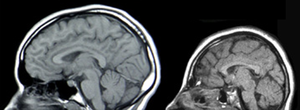

There are three main causes of CNS injury: stroke, traumatic brain injury (TBI), or developmental complications. Strokes are classified as either hemorrhagic (when a vessel is damaged to the point of bleeding into the brain) or ischemic (when a clot blocks the blood flow through the vessel in the brain). When a hemorrhage occurs, blood seeps into the surrounding tissue, resulting in tissue death, while ischemic hemorrhages result in a lack of blood flow to certain tissues. Traumatic brain injury is caused by external forces impacting the cranium or the spinal cord. Problems with CNS development results in abnormal tissue growth during development, thus decreasing the function of the CNS.[3]

Normal Brain Development (left), Microcephaly, a type of encephalopathy (right)